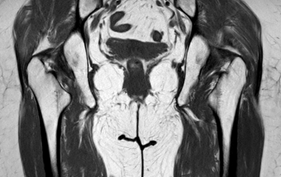

Female patient, 59 years old, followed in Rheumatology for Rheumatoid Arthritis since she was 38 years old. She went to the Rheumatology appointment due to pain, with limitation in abduction, internal and external rotations of the right coxofemoral joint and changes in gait pattern. MRI of the hip joints was requested, which revealed a significant reduction in the space between the lesser trochanter and the ischial tuberosity (Figure 1), with a significant change in the MRI signal of the right quadratus femoris muscle, which presents SPAIR hypersignal translating edema (Figure 2). These aspects are compatible with right ischiofemoral impingement. Rest, analgesic treatment and Physiatrist appointment were recommended. The patient is undergoing physiotherapy. It was prescribed ultrasound, laser, massage, pelvic muscle strengthening and stretching.

Figure 1 MRI of the hip joints reveals a reduced distance between the lesser trochanter of the femur and the right ischium.